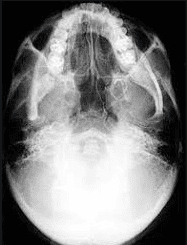

• Chụp X-quang Hirtz (chụp x quang tư thế cằm- đỉnh phim): giúp nhận biết tình trạng của xoang sàng trước, xoang sàng sau và xoang bướm.

2.2. Chụp X-quang Hirtz (chụp x quang tư thế cằm- đỉnh phim) thực hiện như thế nào?

Để chụp X-quang Hirtz người bệnh sẽ được hướng dẫn nằm ở tư thế ngửa đầu sao cho đầu thả khỏi thành bàn để đỉnh đầu chạm vào phim, tia X đi từ trên xuống dưới.

Để thu được hình ảnh chuẩn xác, phục vụ tốt cho việc chẩn đoán, phim phải được đặt cân đối 2 bên phải và trái. Vách ngăn mũi chiếu thẳng giữa 2 răng số 1. Hình chiếu hai xoang sàng trước và sau trên cùng một bình diện, mốc phân định là khe 2 răng hàm số 6 và 7. Cung hàm trên và hàm dưới trùng nhau thành một hình vòng cung.

Trong điều kiện bình thường, hình ảnh các xoang sàng trước và sau sáng đều, các vách ngăn của các tế bào sáng rõ.

Nếu xoang mắc bệnh lý, các tế bào sàng mờ đều hoặc đặc do có mủ, niêm mạc dày, polyp trong xoang. Nếu các vách ngăn sàng không rõ, bị mất đi hoặc bị phá hủy, có thể người bệnh bị polyp mũi hoặc u ác tính.